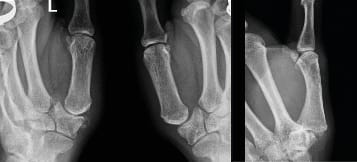

The standard frontal and lateral projections required to achieve good visualisation of the joint have been thoroughly described by Kapandji [9], Kapandji AI, Moatti E, Raab C. La radiographie spécifique de l’articulation trapézo-métacarpienne. Sa technique, son intérêt. Ann Chir Main 1980;34:719-26.[10] Kapandji TG, Kapandji AI. Nouvelles données radiologique sur la trapézo-métacarpienne. Résultats sur 330 dossiers. Ann Chir Main 1993, 12 , N°4, 263-274 and these are still an excellent reference. A posteroanterior projection (Figure 1) is used for the frontal view otherwise the metacarpophalangeal and interphalangeal joints would be visualised first (Figure 1). The lateral view is achieved through an ulnar to radial projection (Figure 2). Across the Atlantic, variations to these projections exist and some useful additions are made. Robert’s view [11] Robert P. La radiographie de l’articulation trapézo-métacarpienne. Les arthroses de cette jointure. Bulletins et mémoires de la Société de Radiologie Médicale de France. 1936;24:687-90. is a variant of the Kapandji frontal view that uses an AP rather than PA projection and is very popular in the English-speaking world. We should not forget comparative images, such as the Eaton view with and without stress. To assess the triscaphoid it is important to include Gedda’s view [12] Gedda KO (1954). Studies on Bennett’s fracture: anatomy, roentgenology and therapy. Acta Chirurgica Scandinavica, 193(Suppl): 1. , also known as Bett’s view [13] Taleisnik J. The Wrist, 1st edn. New York, Churchill Livingstone, 1985: 95–96. , among dynamic views in ulnar and radial deviation. We will move on to a detailed discussion of the key views and their positioning.

Kapandji’s frontal view equates to the Eaton view without stress, and involves placing the thumb in extension while moving the wrist into slight ulnar deviation (Figure 3). This offers good visualisation of the trapeziometacarpal joint.

Eaton’s views are the same as Kapandji’s frontal view, except that in the Eaton series the images are comparative (Figure 4), which means that a stress view (Figure 5) is taken so that the joint space can be assessed for any collapse when put under stress.

In 1936 the French radiologist Robert [8] Vigouroux F, Rabarin F, Jeudy J, Bigorre N, Saint Cast Y, Pechmajou L, Raimbeau G. Peritrapezial osteoarthritis: Inter – and intraobserver reliability of the Allieu classification. Hand Surg Rehab 36 (2017) 363-367 (Figure 6) described an anteroposterior view of the TMC performed in maximum anteroposterior pronation that it is useful to be familiar with. This view is very popular in the USA. It is taken with the patient’s back facing, avoiding irradiating the lower limbs.